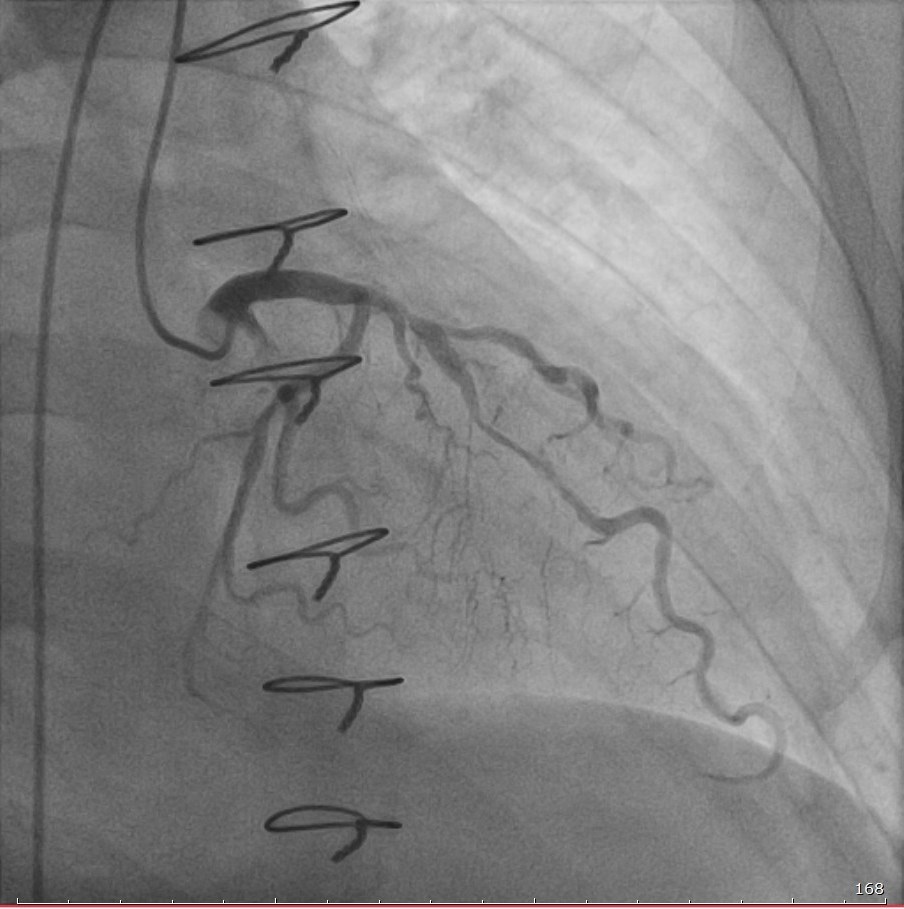

С учётом сложности случая и ранее установленного стента врачи ГКБСМП провели телемедицинскую консультацию с федеральным центром. По рекомендациям специалистов выполнена коронарография и начата гормональная терапия. В ходе вмешательства пациенту имплантированы три стента с лекарственным покрытием, что позволило предотвратить инфаркт и купировать признаки отторжения.